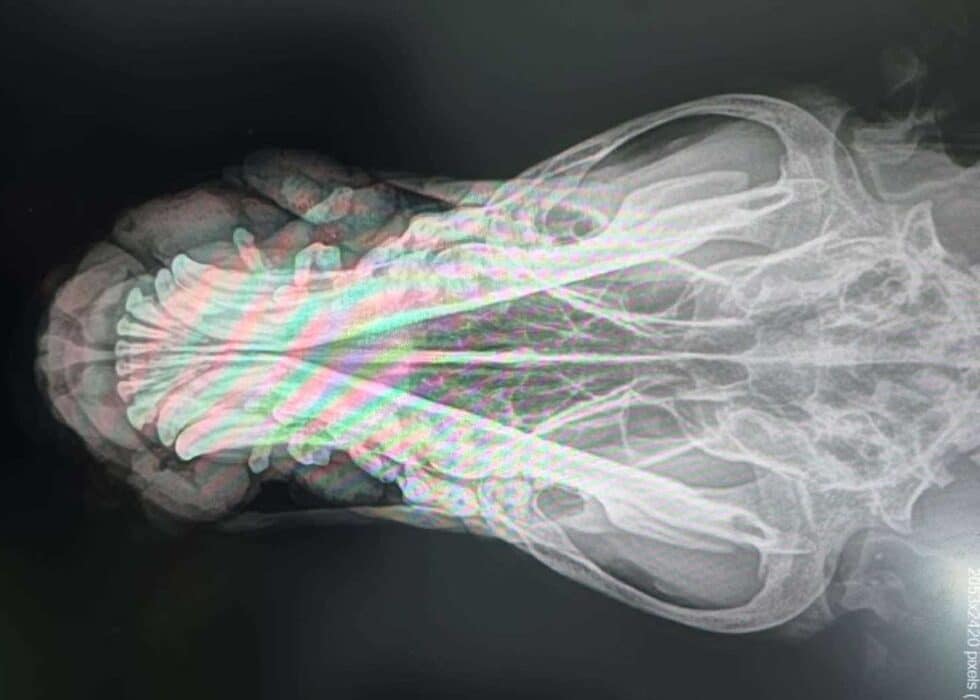

Leider gibt es traurige Nachrichten von ARON aus Rumänien. Bei dem tollen Schäfi wurde ein Tumor diagnostiziert. In der Klinik wurden Röntgenaufnahmen gemacht, die gezeigt haben, dass sich bereits Lungenmetastasen gebildet haben.